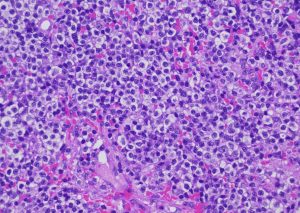

上皮向性リンパ腫は一般の獣医師だと生涯で1回診るかどうか?位だと思います。もし出会っていても生検までして確定診断に至っていない事も多いでしょう。当院では皮膚科認定医として広く来院頂いているので割と診断と治療をします。先日も新しい子で診断したのですが、悲惨な話が多いですが必ずしも予後不良とは限らないよ!と言うエールのつもりで書きました。他の症例も早くアップしなくちゃいけないんですが・・・。